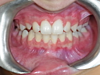

Cas 3

Enfant de 7 ans, occlusion inversée des incisives corrigée par des plaques à pistes de Planas.